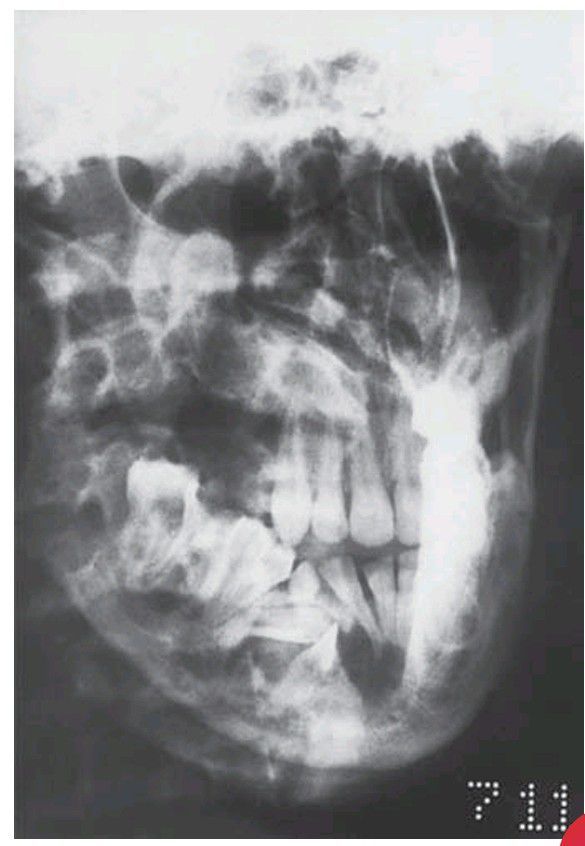

Oblique lateral radiograph of a patient with the basal cell naevus (Gorlin’s) syndrome. A very large odontogenic keratocyst involves the whole ramus and body, causing considerable expansion, especially at the lower border.